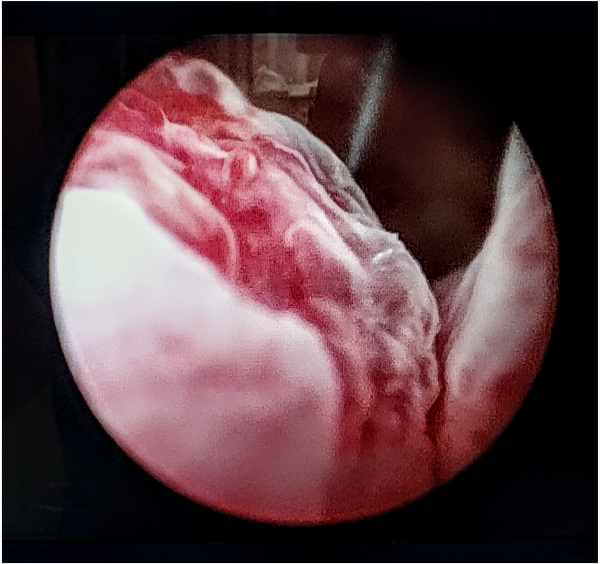

Ischemic incisions following treatment with #iTind. Learn more at iTind.com. # BPH #ReshapingBPH #OlympusUrology #urology